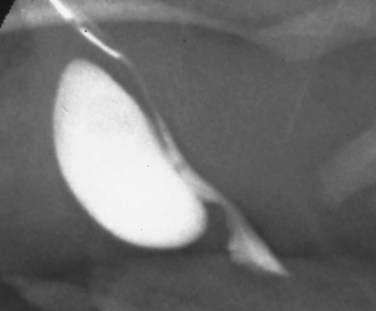

High voiding pressures distend and thin the prostatic urethra. The storage capacity of the prostatic urethra sometimes exceeds that of the bladder because of the relative lack of muscle there. The verumontanum is distorted, and the ejaculatory ducts may be dilated from refluxing urine. The bladder neck is rigid and hypertrophied (Fig. 126–4). This high bladder neck was once mistaken as another cause of obstruction and was surgically incised to facilitate bladder emptying. Unfortunately, this practice often resulted in total incontinence. Today it is understood that the appearance of the bladder neck is a result of distal obstruction and not obstructive lesion itself. Bladder neck appearance and function usually improves after the obstructive valves are destroyed.

Figure 126–4 A, Voiding cystourethrogram shows a posterior bladder diverticulum near the base of the bladder and an extremely high bladder neck. A catheter passed blindly can fail to pass over the bladder neck and coil in the dilated posterior urethra. B, Massive vesicoureteral reflux in a boy with valves.